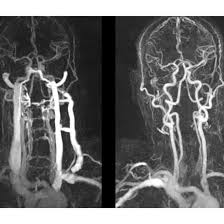

CT Head & Neck Angiography

Medifyhome is committed to delivering precision and comfort in diagnostic imaging. With state-of-the-art CT technology, we provide clear and accurate visualizations of the vascular system in the head and neck. Our team of skilled radiologists ensures that each scan is interpreted with the maximum level of accuracy. And from convenient appointment scheduling to reporting on time, we streamline processes for a stress-free experience. Low prices and a focus on the patient make Medifyhome a trusted partner for advanced diagnostics.